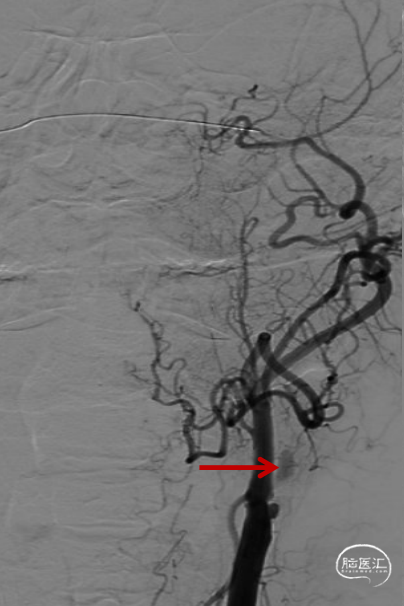

交换出微导管及多功能导管,C2段放置SPIDER保护伞后以3-30mm球囊和6F 115cm SKATHI远端通路导管采用球囊接力技术越过颈内动脉闭塞段,由下及上持续抽吸。

抽吸状态下整体撤出保护伞,继续抽吸,血栓堵塞SKATHI导管及导引导管,负压下整体将系统撤出,可见大量血栓。

回撤SKATHI远端通路导管至C3段,通过导管再次释放SPIDER保护伞,回撤导管至颈总动脉,造影见C1段严重狭窄,以4-30mm球囊扩张狭窄段,复查造影狭窄段好转,远端再次闭塞,考虑斑块或血栓脱落,立即置入7-40 wallstent支架。

复查造影远端仍然闭塞,负压状态上行SKATHI远端通路导管回收保护伞并抽吸血栓,可见保护伞及大量血栓取出,复查造影C3段仍有血栓。再次上行SKATHI远端通路导管抽吸取栓,复查造影示远端血流通畅。